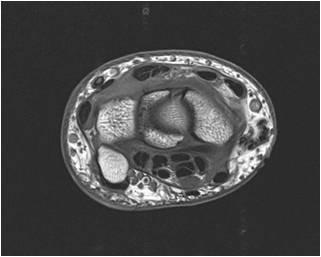

Radiograph #3

Wrist and Carpal Tunnel

Identify: Median nerve, flexor pollicis longus, pisiform, scaphoid, flexor carpi radialis, extensor pollicis brevis, extensor pollicis longus, radial artery, palmaris longus, ulnar artery, triquetrum.